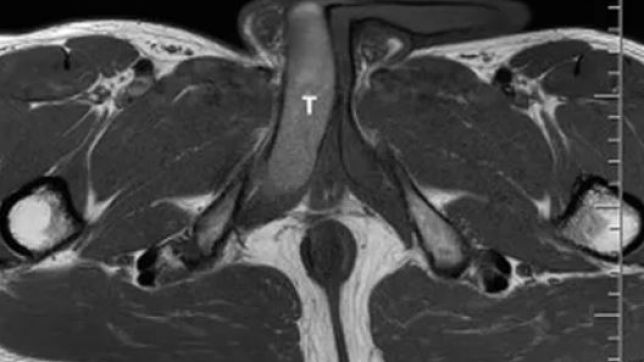

Depois de um treino de corrida, o eslovaco percebeu um caroço no pênis. Na mesma noite, ele começou a ter ereções dolorosas. Os exames mostraram um coágulo de 18 milímetros, e foi diagnosticado com uma trombose parcial nos corpos cavernosos do pênis (tecidos eréteis esponjosos que recebem sangue).

Três anos depois, exames ainda detectaram um coágulo residual, mas o paciente já estava sem sintomas. Segundo os médicos, casos assim requerem acompanhamento de no mínimo um ano para evitar que o coágulo cause outras complicações. Depois do tratamento, o pênis do homem continuou capaz de manter ereções normalmente.

/i.s3.glbimg.com/v1/AUTH_1f551ea7087a47f39ead75f64041559a/internal_photos/bs/2023/v/N/IJzATrS3yw5huVdP7G4Q/1-s2.0-s2214442023003017-gr2.jpg)

Foto: Reprodução